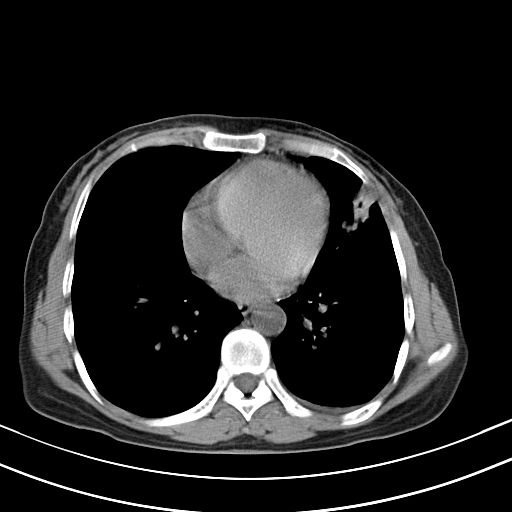

女,47岁,咳嗽胸痛一个星期,我们考虑肺结核,左下肺病灶肿瘤像不像,请高手指点。急。

考虑两肺炎症,左胸腔积液,建议治疗后复查!

考虑炎性病变,左肺舌叶病灶需要与早期肺脓肿鉴别(结合实验室),左侧少量胸腔积液。

1)右肺上叶前段及左肺上叶舌段感染性病变;建议抗炎治疗后复查。2)左侧少量胸腔积液。